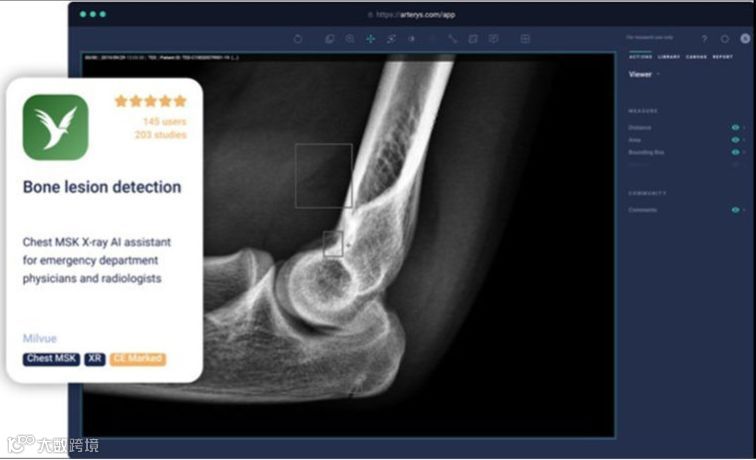

五、Arterys:Arterys Marketplace

Arterys在RSNA 2019上首次展示了其开放式创新平台Arterys Marketplace。该平台希望能让全球各地的人都可以使用医学影像AI。总部位于旧金山的Arterys表示,任何人只需访问互联网就可以将AI模型转换成影像医生的临床应用程序。Arterys上可用的开发者工具包括带有阅片器的在线环境部署、可扩展的后端、无缝集成工程和支持FDA批准的实验性AI模型。Arterys表示,在过去七年里,它投资了超5000万美元用以开发Arterys Marketplace和临床级的Web端阅片器。Arterys允许全球各地的开发者在Arterys Marketplace上共享开发内容,并提供了一套标准。Arterys鼓励开发者多使用Arterys Marketplace并去推动普通人也开始使用并与AI互动。